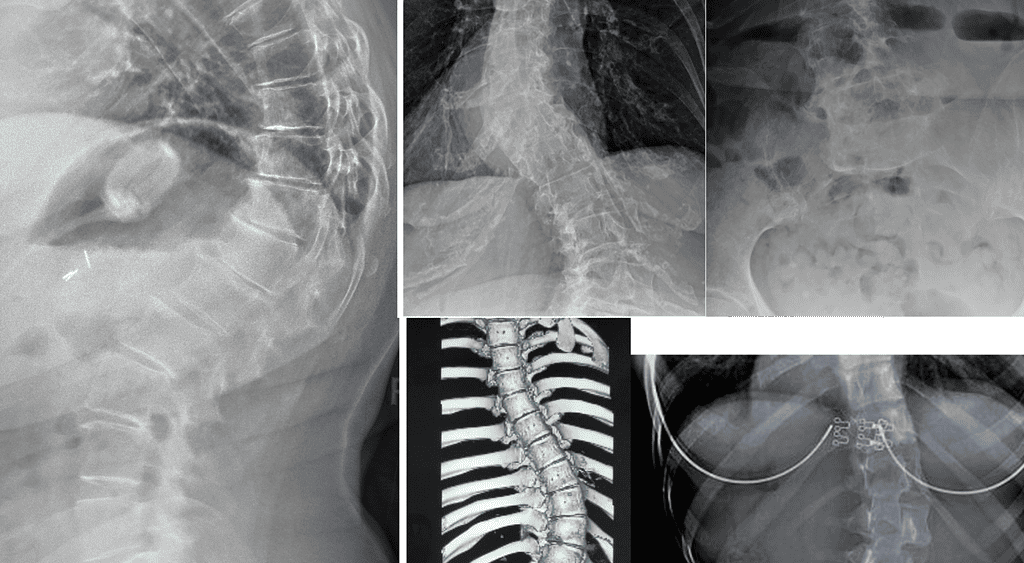

Measurable outcomes on X-ray. Here is what our co-managed patients have experienced.

Note: Individual results vary. All measurements taken on calibrated standing AP radiographs by the treating doctor. Cases shown with patient/guardian consent.

In-Brace Correction is normally 48% but we could see 63%.*

Out-of-Brace curves achieved 37.60% improvement if their curves are 20°-40°.

Results: curve correction: 76.9%, curve stabilization: 23.1%, curve progression 0%